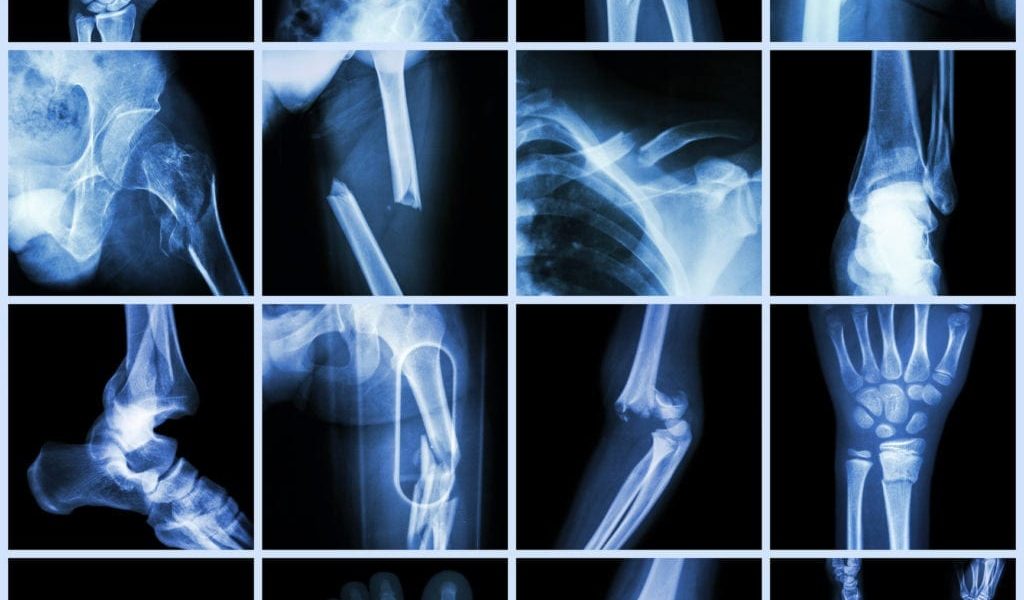

For an ankle fracture to fully heal, the joint must be stable and the only way to determine this is with x-rays.